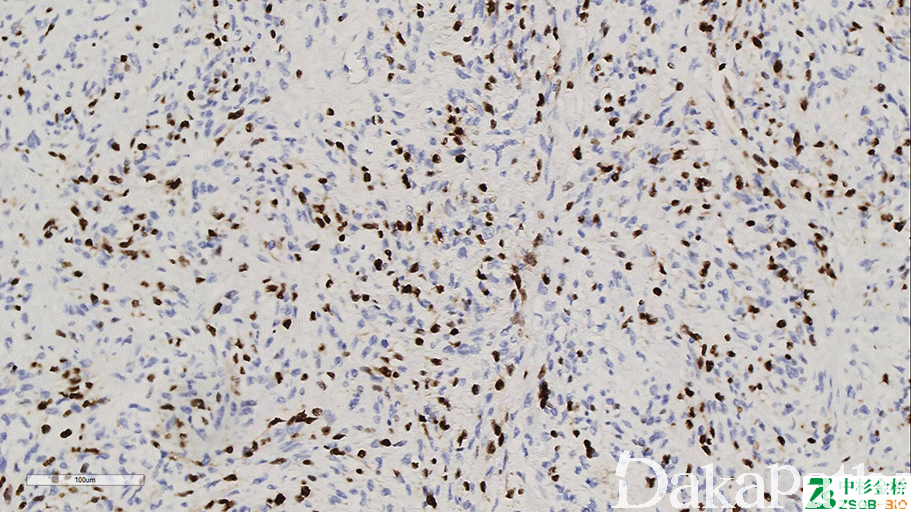

Myogenin

肌源性转录调节蛋白,仅在有横纹肌分化的细胞有表达且胞浆分化越明显的细胞表达越弱。

信号定位: 胞核

几乎全部阳性(≥95%的病例阳性): 腺泡状横纹肌肉瘤、葡萄状横纹肌肉瘤、上皮样横纹肌肉瘤、胚胎性横纹肌肉瘤